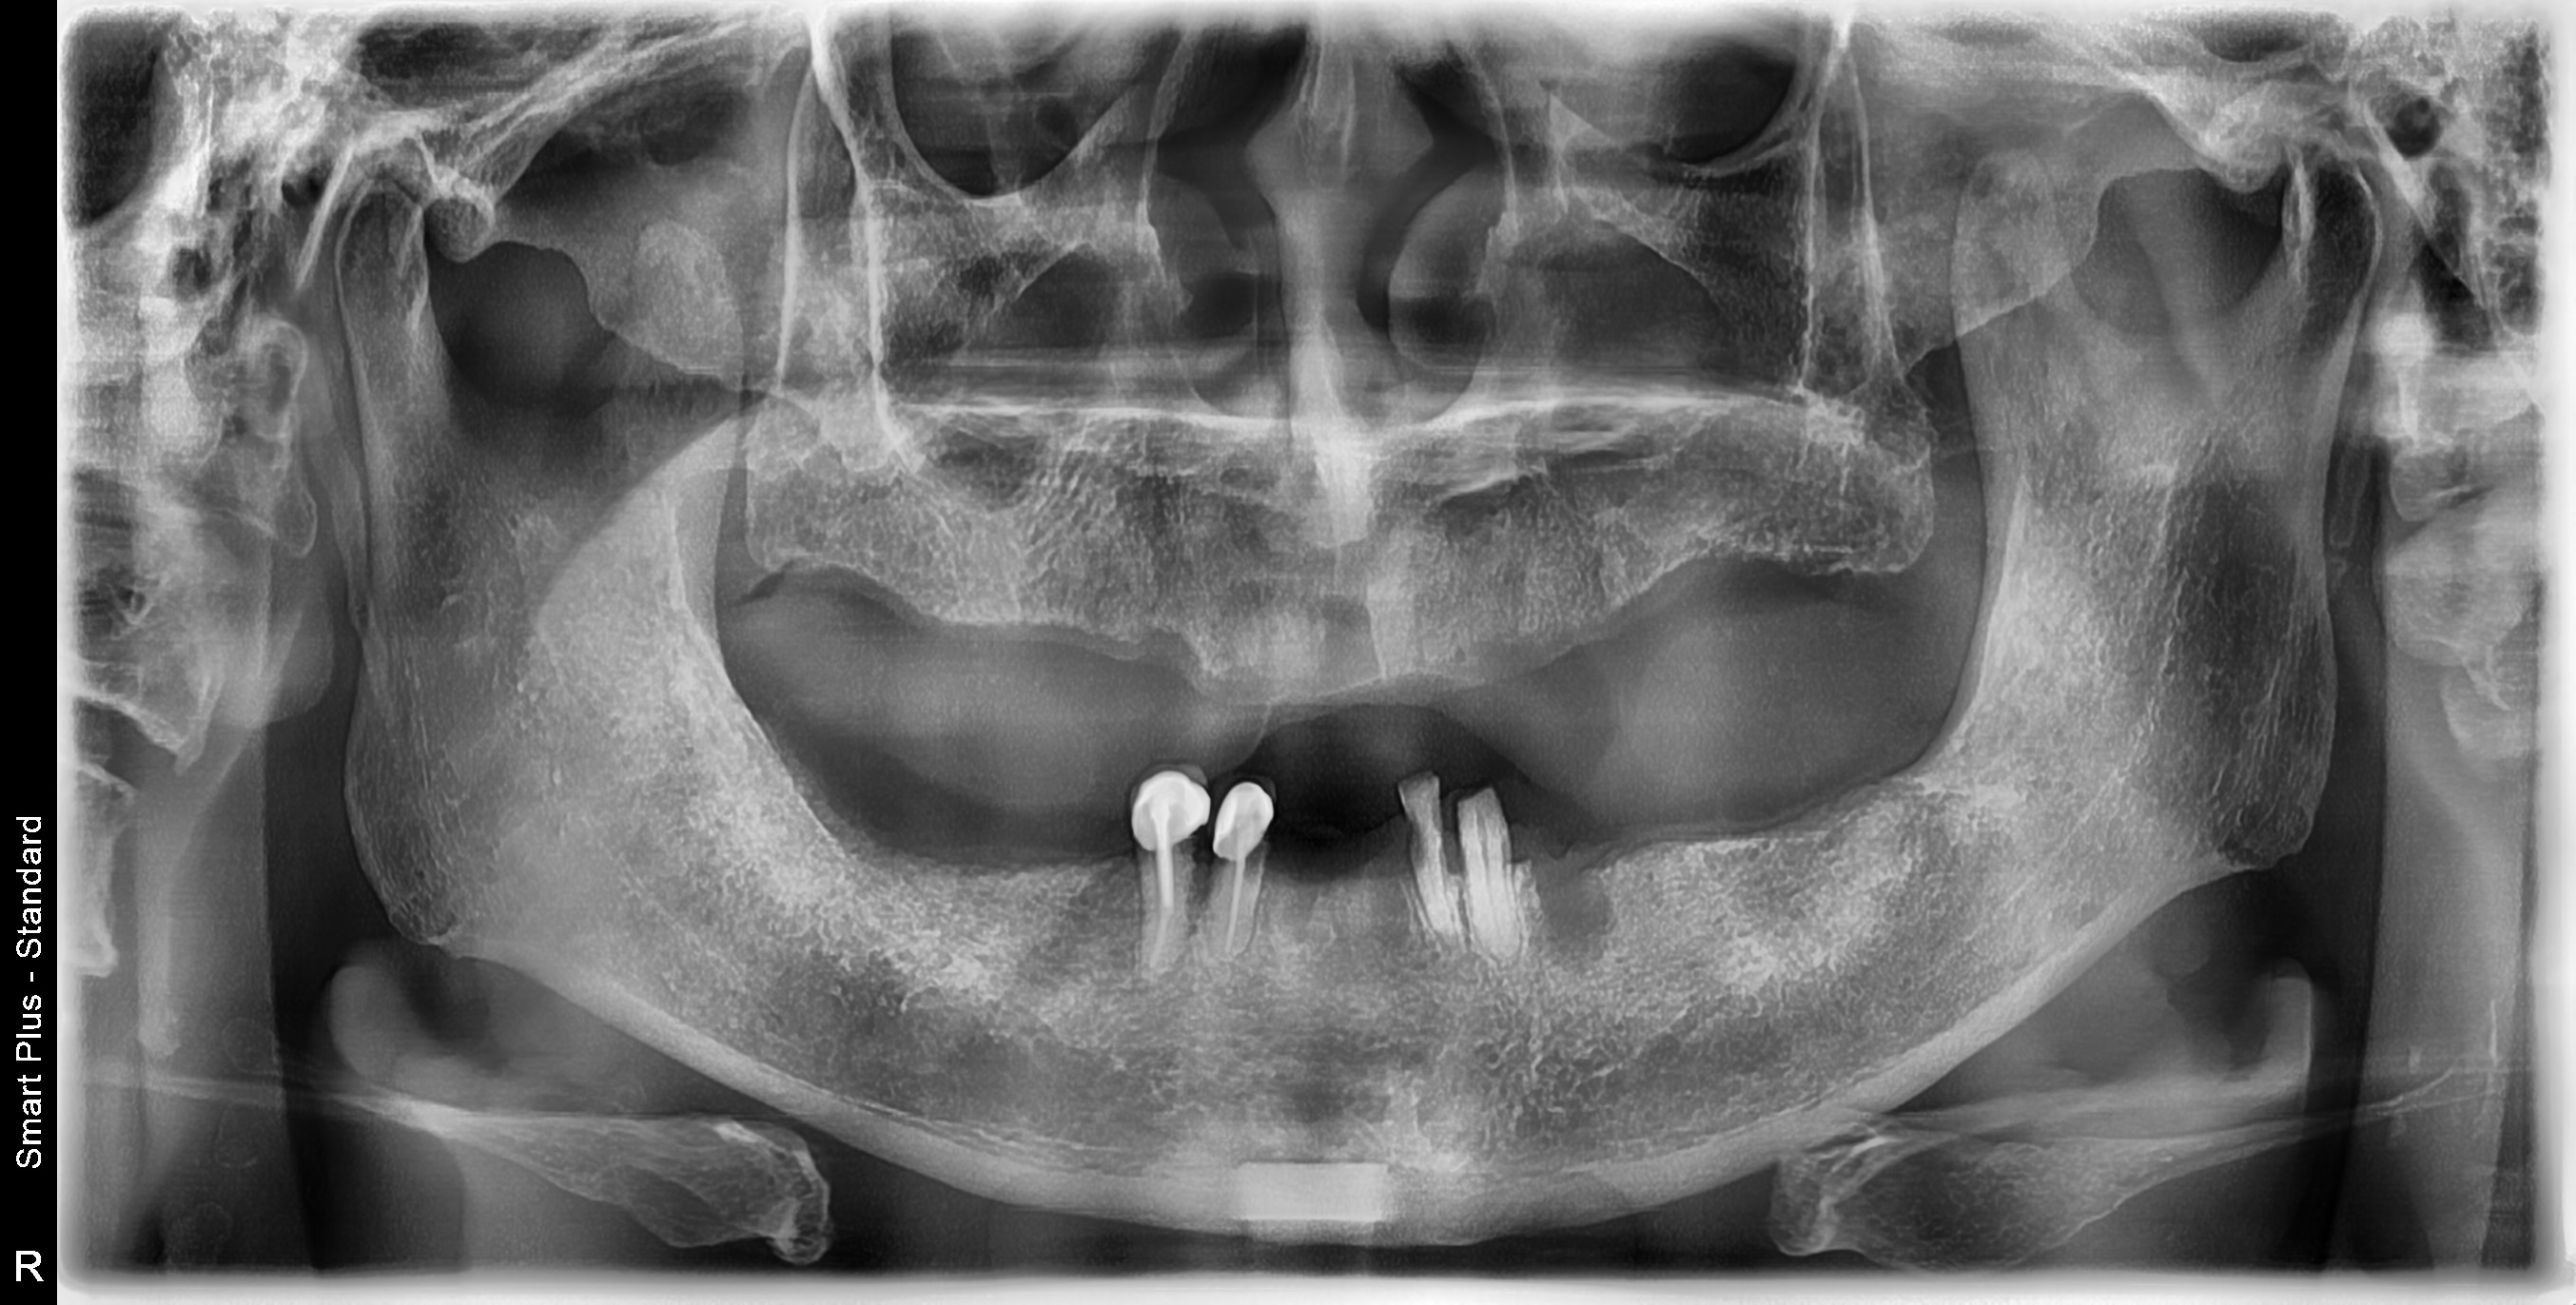

Before